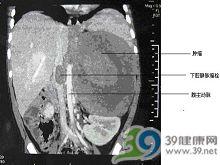

3.CT檢查 由腹部腫瘤所致阻塞採用CT檢查可明確阻塞的平面範圍另外對病變性質也能大致做出診斷CT結合對比劑的套用可清楚顯示不同平面的血管管腔精確診斷腔靜脈阻塞部位程度和可能的原因側支循環通路靜脈擴張度等 。

4.B超檢查 B超檢查在診斷下腔靜脈阻塞中起重要作用中山醫院19例肝段下腔靜脈阻塞的病人B超檢查結果與下腔靜脈造影基本相同1例下腔靜脈合併上腔靜脈阻塞X線造影顯示下腔靜脈在第9胸椎上緣水平處阻塞因上腔靜脈阻塞無法插入導管造影不能確定病變範圍但B超檢查發現在距心臟入口約20mm處下腔靜脈內有4mm厚的隔膜B超檢查準確方便甚至有時可彌補造影的不足並可篩選病人作下腔靜脈造影的主要檢查方法可見肝臟腫大腹水等